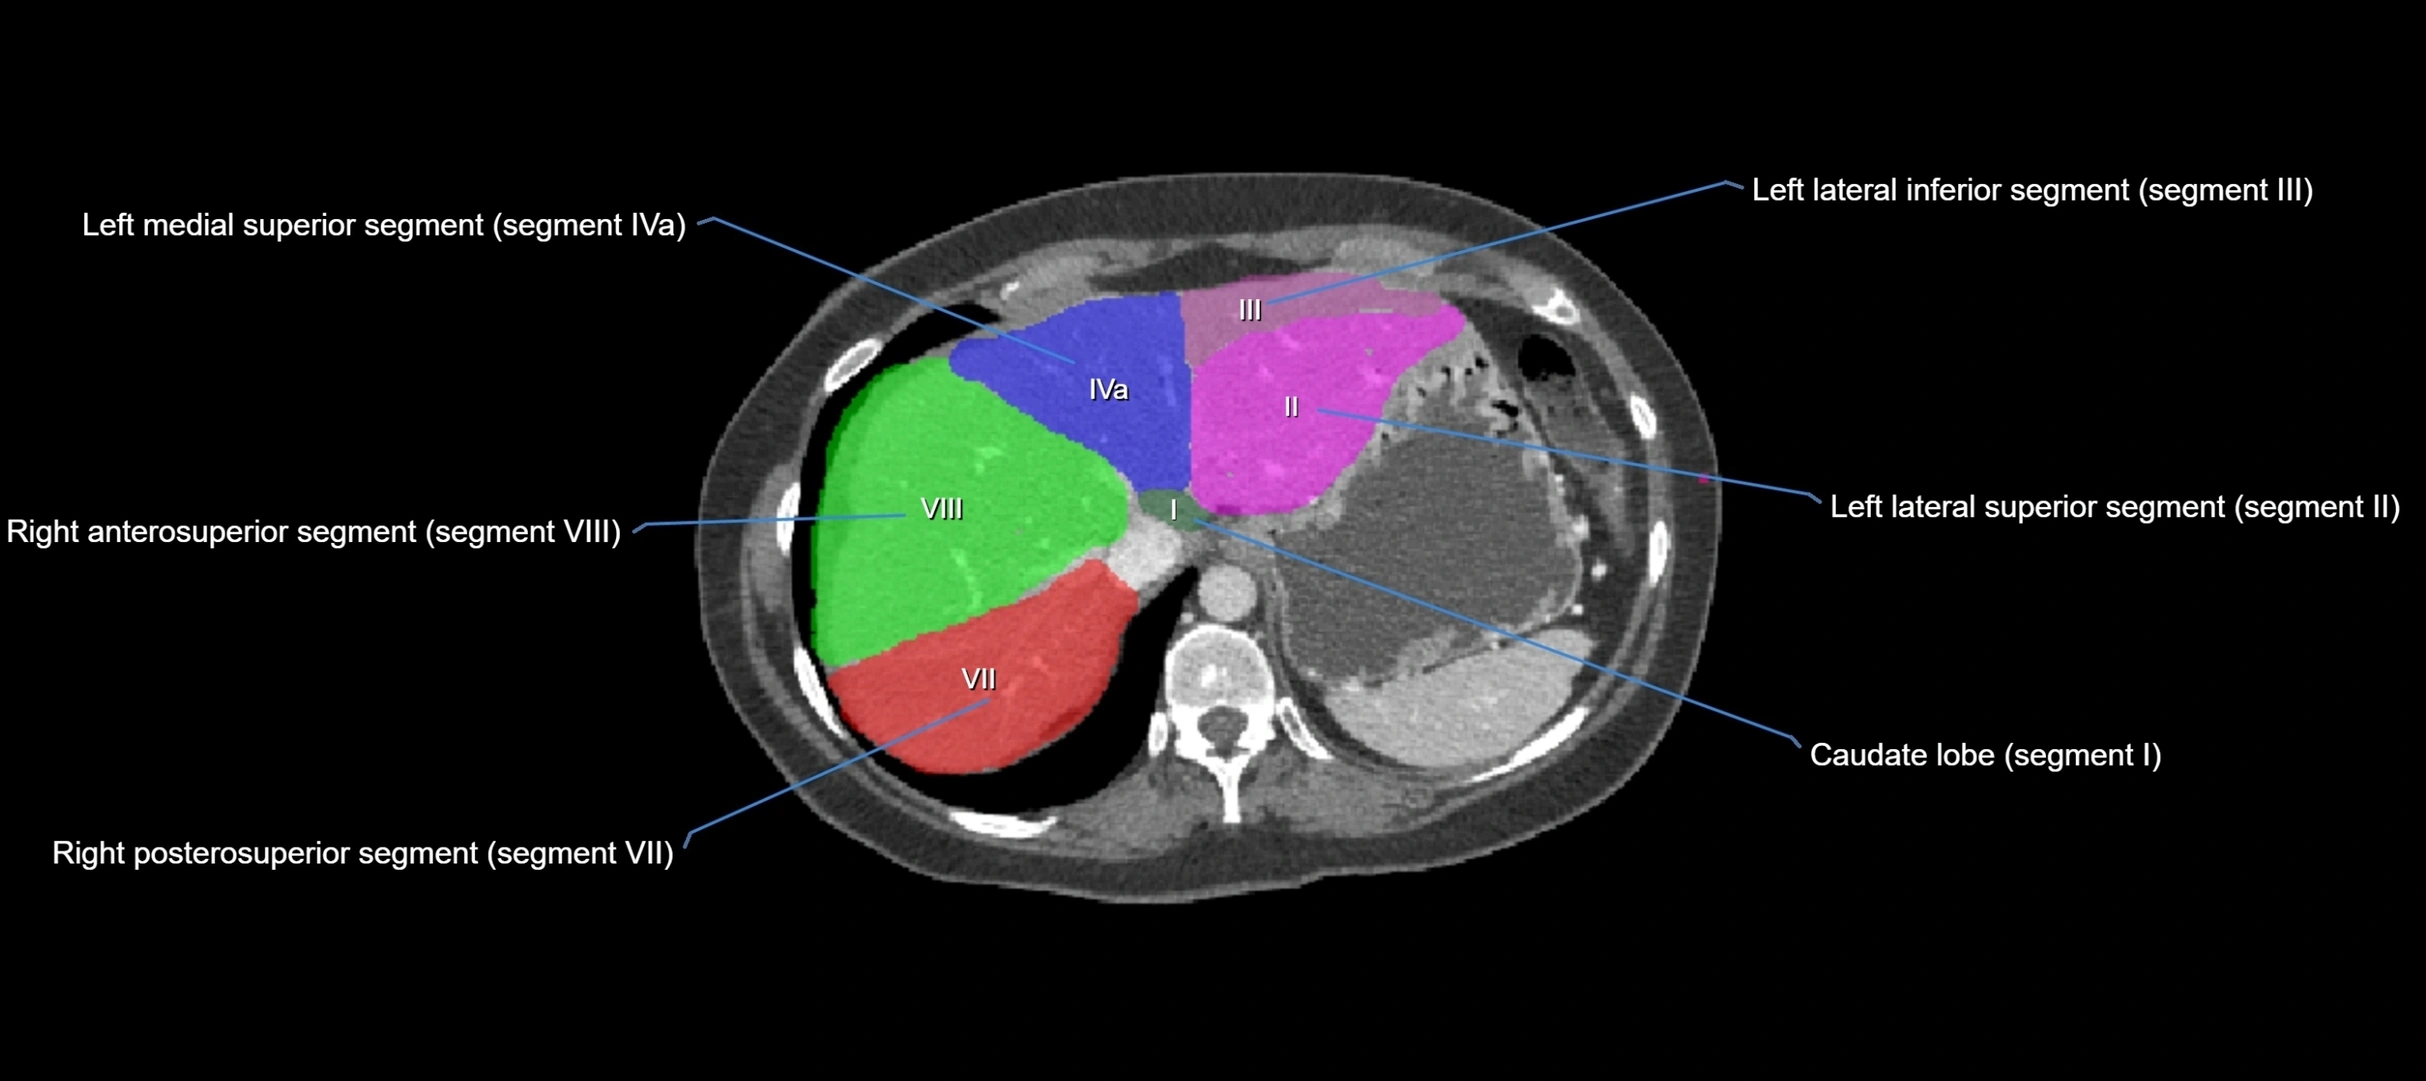

The caudate lobe of the liver is a distinct anatomical subdivision of the liver, designated as segment I in Couinaud’s classification. It lies on the posterior surface of the liver, between the fissure for the ligamentum venosum (left boundary) and the groove for the inferior vena cava (IVC) (right boundary). Superiorly, it is related to the posterior liver surface, and inferiorly it is separated from the left lobe by the porta hepatis.

The caudate lobe is unique because it receives dual portal venous and arterial inflow from both the right and left portal veins and hepatic arteries. It also has independent venous drainage directly into the IVC via multiple small hepatic veins, unlike other lobes that drain through the three main hepatic veins.

CT Appearance

CT Pre-Contrast:

• Caudate lobe appears as a soft-tissue density, isodense to the rest of the liver

• Enlargement may be appreciated in cirrhosis or Budd–Chiari syndrome

CT Post-Contrast:

• Homogeneous enhancement in the portal venous phase, similar to rest of liver

• Independent venous drainage into the IVC may be visualized

MRI image

image